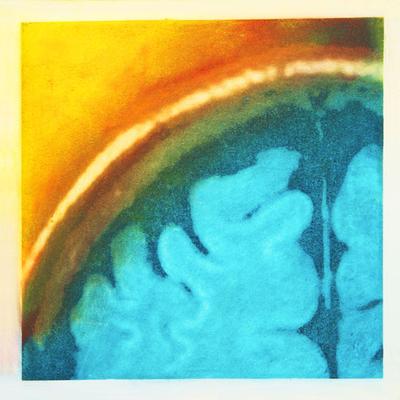

"In “Self Portrait of the Artist’s Brain I,” artist Elizabeth Jameson saturates an MRI with vibrant colors of French dye on silk, to portray herself as a person with energy and passion, despite having a brain disease that threatens those qualities. - See more here." (Clicking link will open a new window).

Although not all of her paintings are of brains - she loves painting flowers, people, or anything else that makes her happy - many are of this complex, and wonderful organ. When she paints her brain art, it helps to give meaning to MS.

She sees the MRI scan of the brain as a symbol of multiple sclerosis. After being diagnosed, she spent a significant amount of time inside those MRI machines getting scan after scan. It only seemed natural that she devote some part of her art to those mesmerizing images that represent so much to every person with MS.

She wanted to somehow change that negative, overwhelming, feeling that each and every MRI evoked. Her art could again bring meaning and beauty to an otherwise devastating situation.